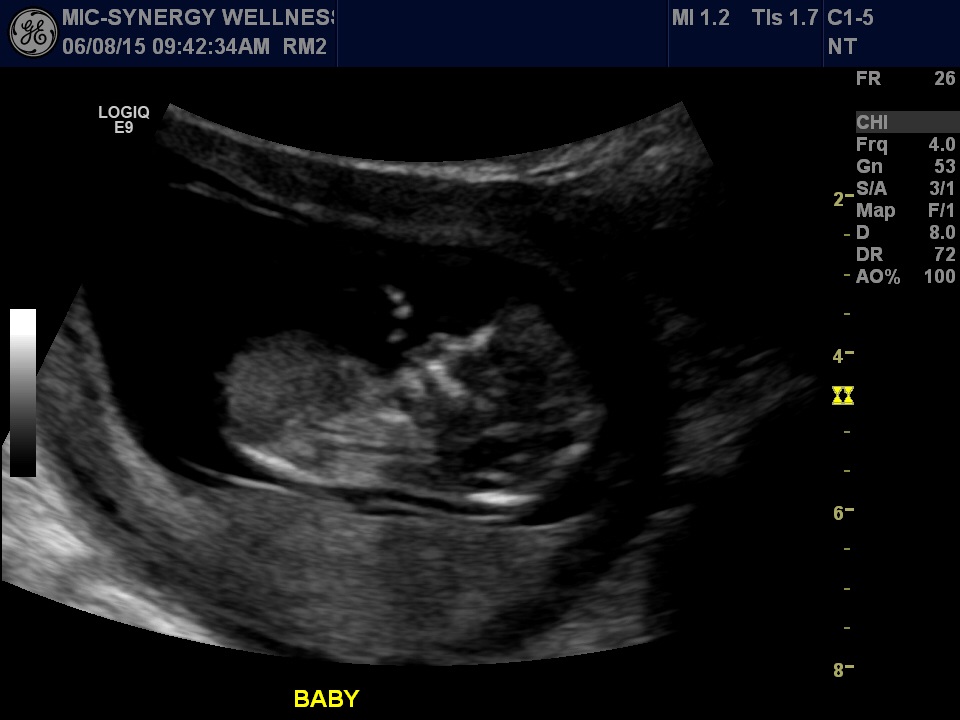

Our little bub at 12+3. What a jumping bean! I was so surprised by how much movement we observed that I couldn't stop laughing. Must be an exhausting life in there!